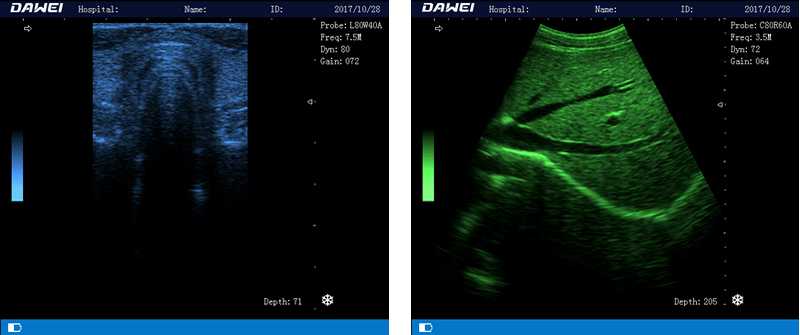

筆記本全數字超聲診斷儀

1.優(yōu)質的數字成像技術,圖像更清晰

5.體積小巧,圖像清晰,操作方便,續(xù)航能力強